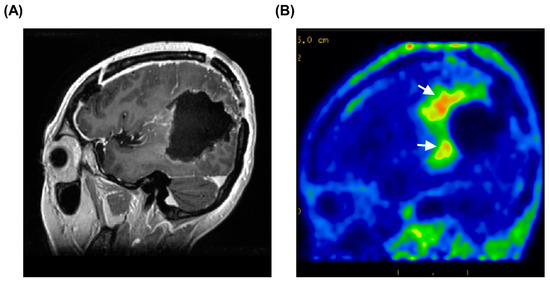

3.5. Representative Case